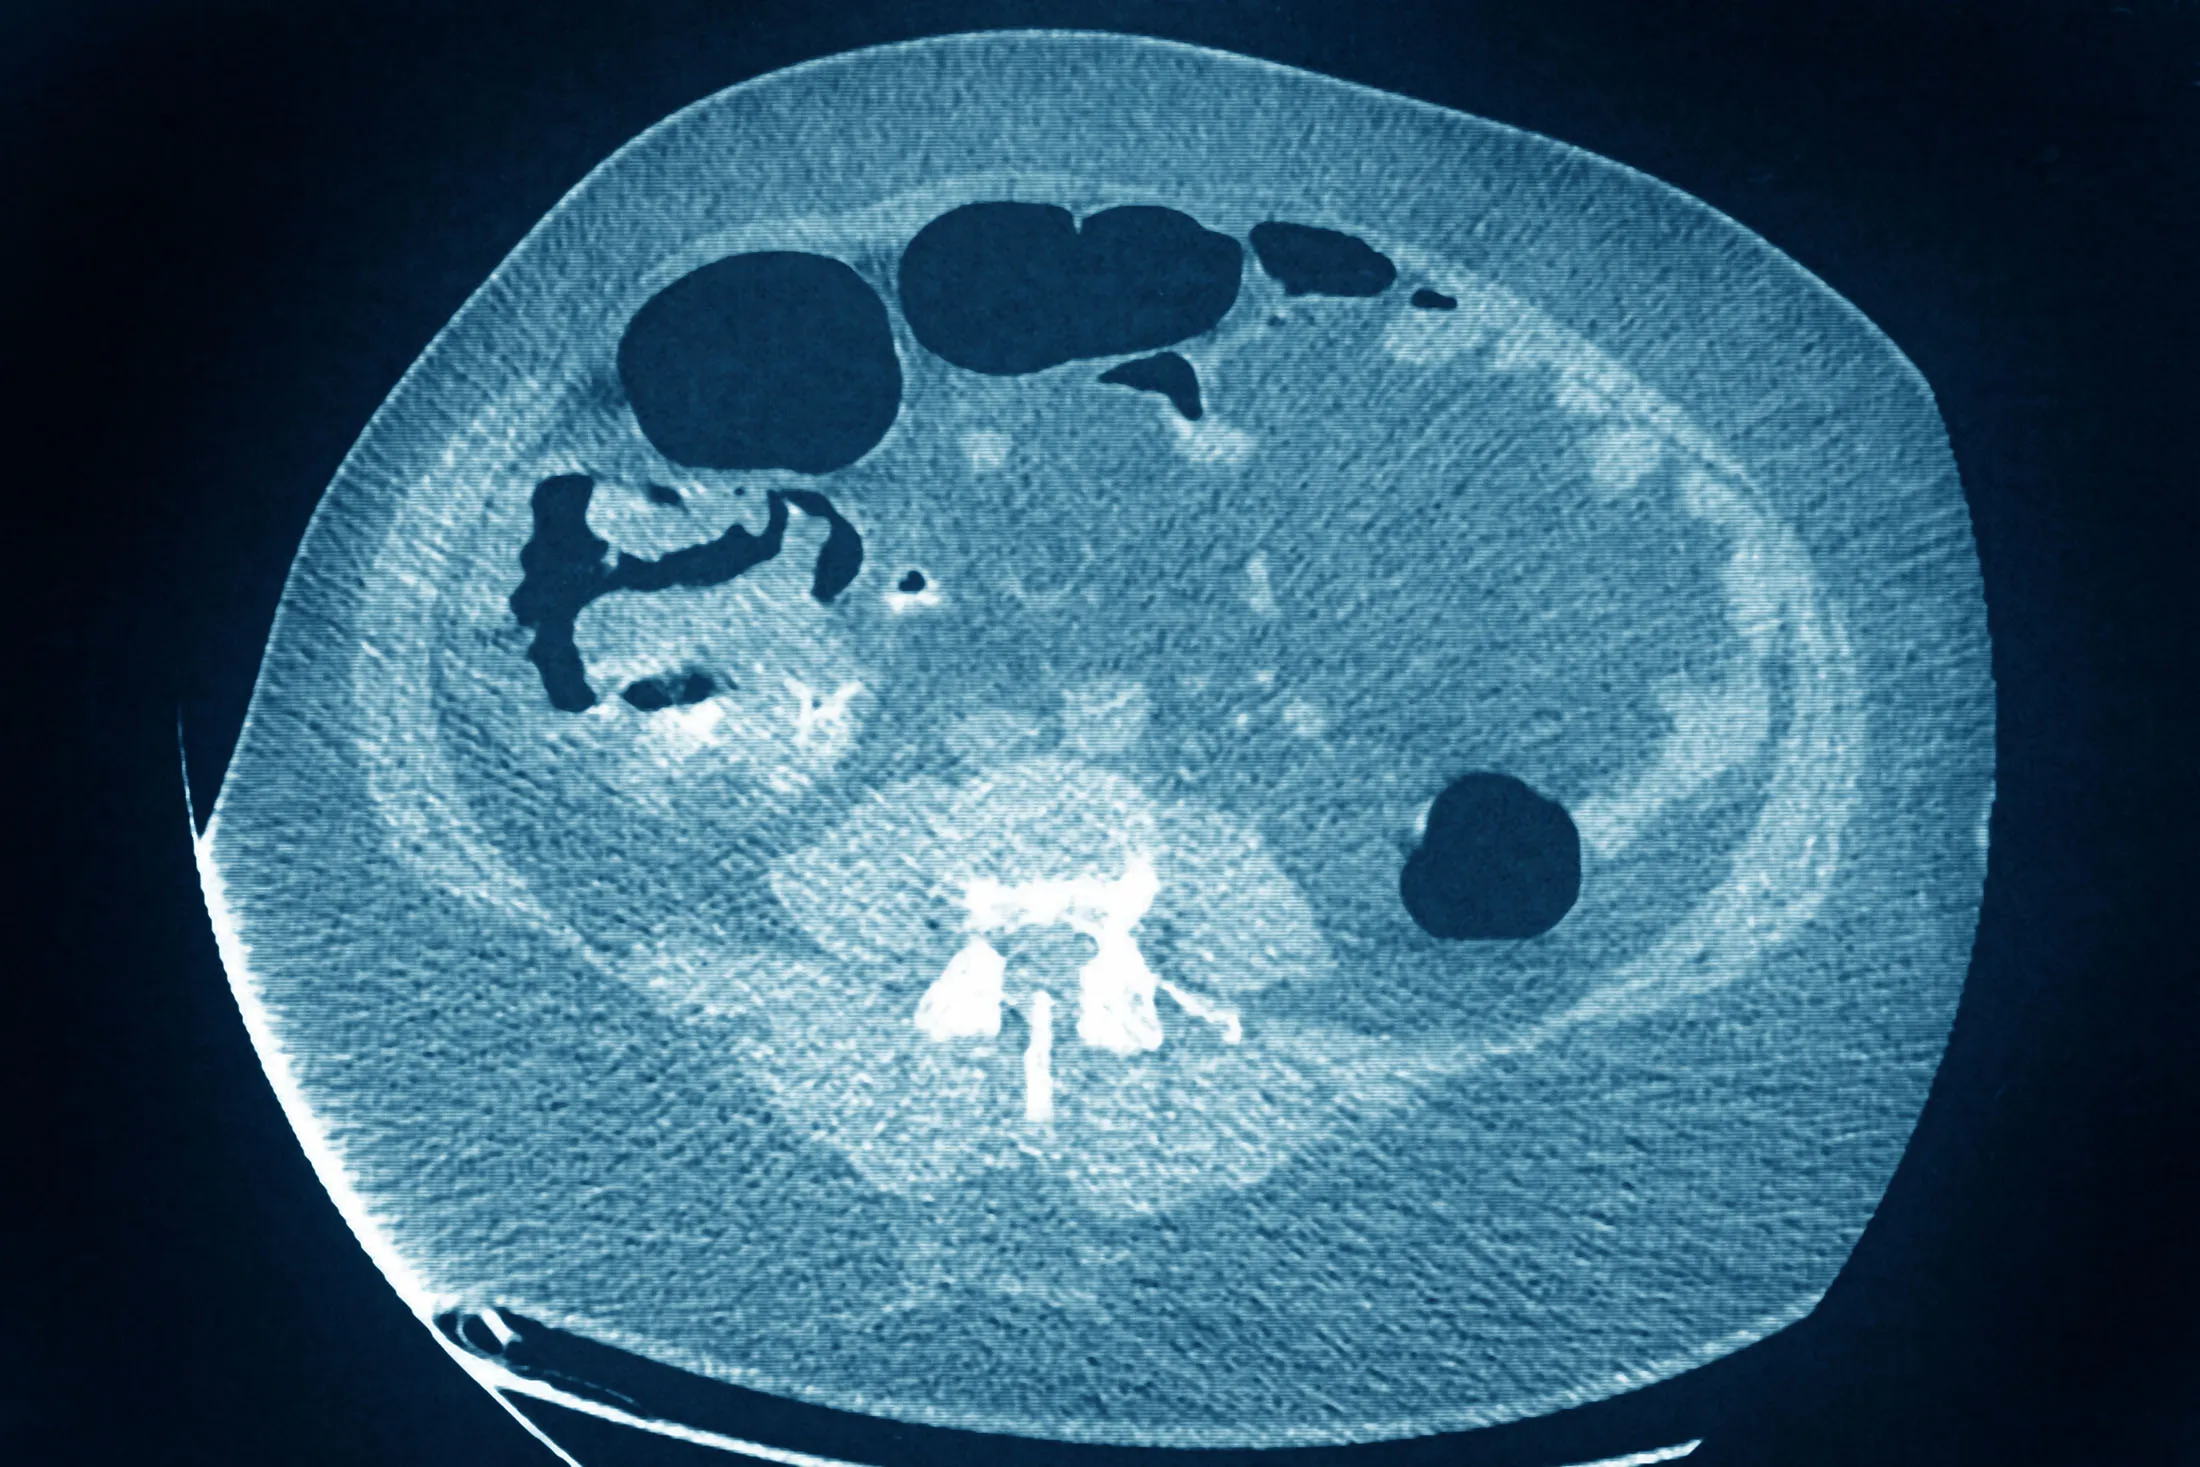

A colon cancer tumor seen on a radial CT scan.

Source: BSIP/Universal Images Group/Getty Images